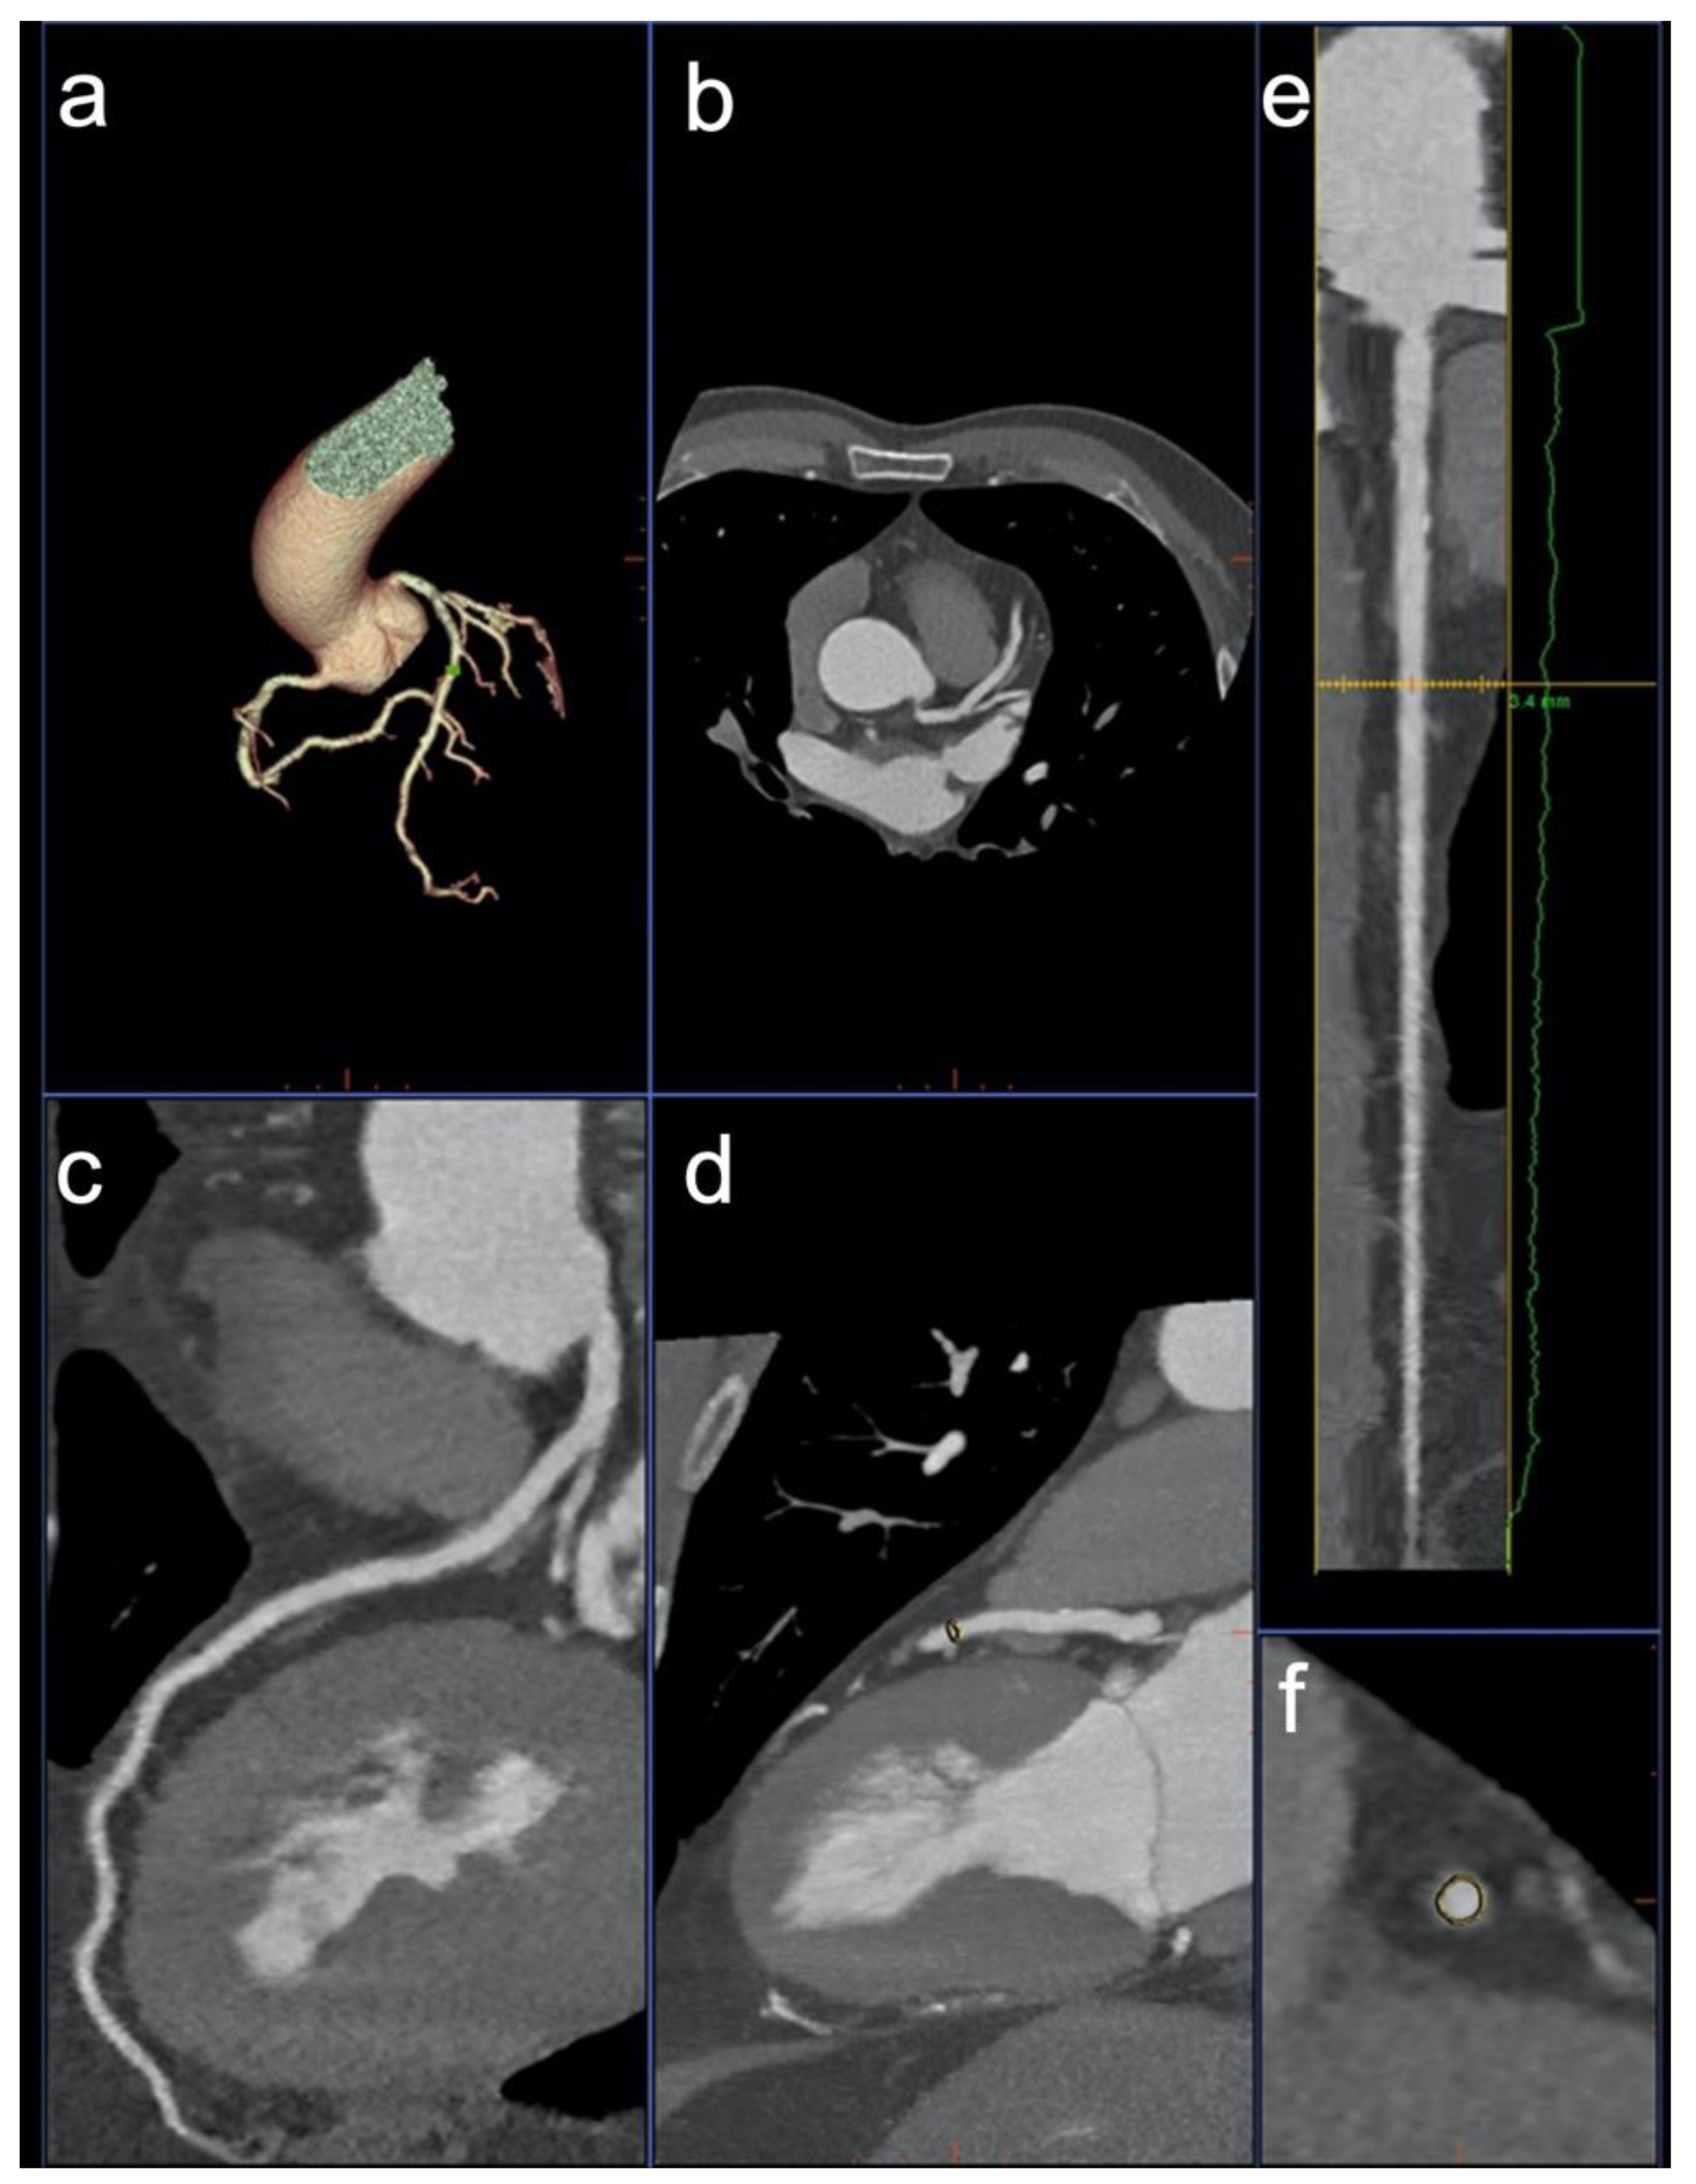

2.3. Image Post Processing—Group 1

2.5. Image Post Processing—Group 2